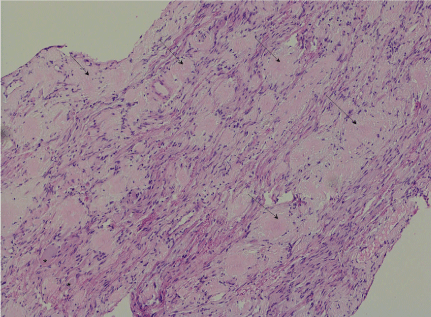

The biopsy from Meckel’s cave showed extensive amyloid deposition both within the nerve with enmeshed myelinated fibres but also in the epineural compartment (Figure 3). There were sparse plasma cells at the edge of the lesion. The extracellular proteinaceous deposit was positive for crystal violet and Congo red staining was positive with typical birefringence and dichroism effects when examined under polarised light. Potassium permanganate pre-treatment only partly obliterated staining with Congo red (Figure 4). Staining for kappa and lambda light chain was not interpretable. Immunohistochemical staining for amyloid-A was weakly positive. The histopathological diagnosis was of an amyloidoma of the trigeminal nerve at the level of the gasserian ganglion.

Figure 3: (H&E x100): There are amorphous pale eosinophilic deposits (arrow) amongst axons and spindled Schwann cells of the trigeminal nerve. Two ganglion cells are at the bottom left (*)